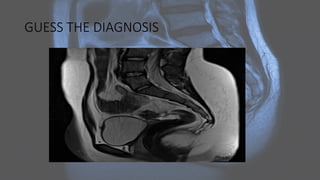

ENDOMETRIAL CARCINOMA

GUESS THE DIAGNOSIS